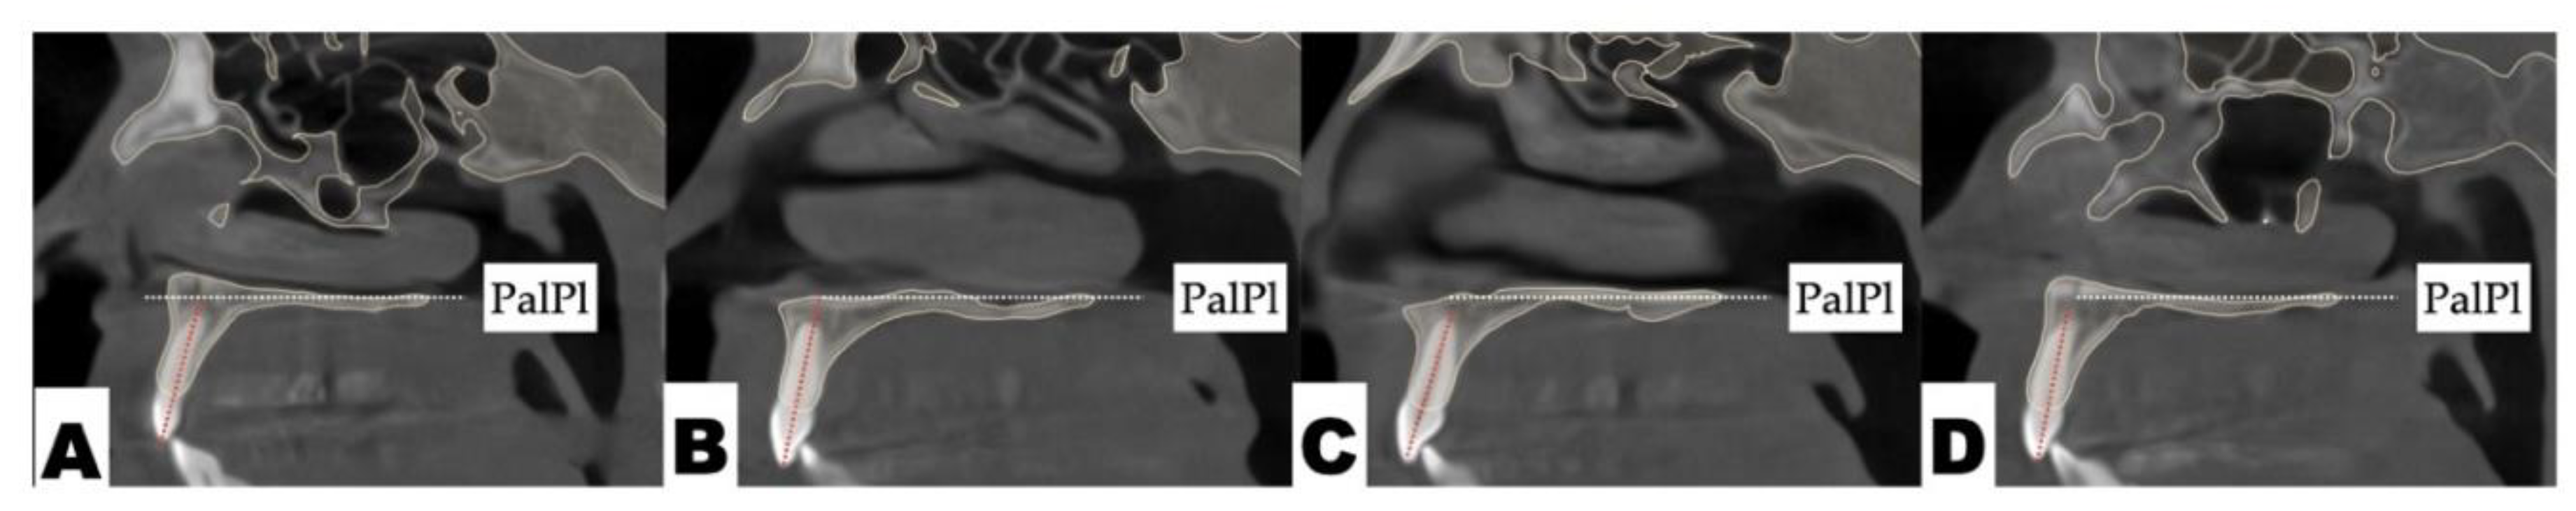

Dental analysis: Differential inclination of the maxillary incisors is shown in Figure 8.

Figure 8. The sagittal view of the axial cross-section of maxillary incisors: A—Maxillary right lateral incisor; B—maxillary right central incisor; C—maxillary left central incisor; D—maxillary left lateral incisor. The axial inclination of the maxillary left incisors is steeper compared to the right side.